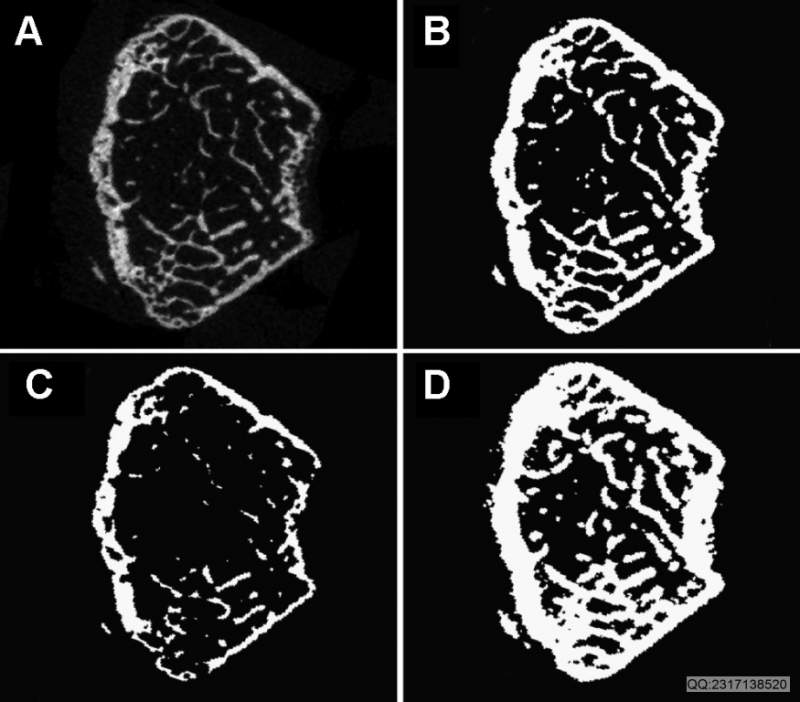

Guidelines for Assessment of Bone Microstructure in Rodents Using Micro–Computed Tomography

Use of high-resolution micro–computed tomography (mCT) imaging to assess trabecular and cortical bone morphology has grown  immensely. There are several commercially available mCT systems, each with different approaches to image acquisition, evaluation, and reporting of outcomes. This lack of consistency makes it difficult to interpret reported results and to compare findings across different studies. This article addresses this critical need for standardized terminology and consistent reporting of parameters related to image acquisition and analysis, and key outcome assessments, particularly with respect to ex vivo analysis of rodent specimens. Thus the guidelines herein provide recommendations regarding (1) standardized terminology and units, (2) information to be included in describing the methods for a given experiment, and (3) a minimal set of outcome variables that should be reported. Whereas the specific research objective will determine the experimental design, these guidelines are intended to ensure accurate and consistent reporting of mCT-derived bone morphometry and density measurements. In particular, the methods section for papers that present mCT-based outcomes must include details of the following scan aspects: (1) image acquisition, including the scanning medium, X-ray tube potential, and voxel size, as well as clear descriptions of the size and location of the volume of interest and the method used to delineate trabecular and cortical bone regions, and (2) image processing, including the algorithms used for image filtration and the approach used for image segmentation. Morphometric analyses should be based on 3D algorithms that do not rely on assumptions about the underlying structure whenever possible. When reporting mCT results, the minimal set of variables that should be used to describe trabecular bone morphometry includes bone volume fraction and trabecular number, thickness, and separation. The minimal set of variables that should be used to describe cortical bone morphometry includes total cross-sectional area, cortical bone area, cortical bone area fraction, and cortical thickness. Other variables also may be appropriate depending on the research question and technical quality of the scan. Standard nomenclature, outlined in this article, should be followed for reporting of results.